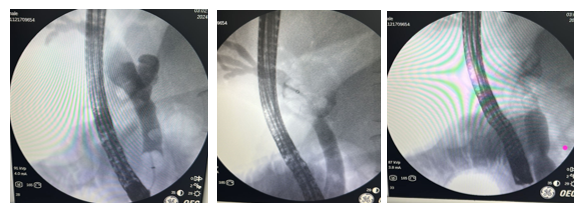

A 40-year-old female patient with a history of ERCP (endoscopic retrograde cholangiopancreatography) for obstructive biliary syndrome caused by a gallstones. The cholangiogram showed a dilated intrahepatic and extrahepatic bile duct (15 mm), with filling defects of 15 mm in the middle common bile duct and 10 mm in the distal common bile duct (7 mm in this area). A papillotomy was performed and the bile duct was explored with an occlusion balloon and Dormia basket, extracting several stones, except for one giant. A bilioplasty was performed with a 15 mm balloon at 3 ATM for 60 seconds, finally achieving the extraction of the giant stone. Confirmatory cholangiogram showed a bile duct free of filling defects (Annex 1). The procedure was completed without complications.

In addition, mild ectasia of the extrahepatic bile duct was documented with a linear image inside it, suggestive of a hepatobiliary endoprosthesis. However, the patient had no history of placement of said endoprosthesis, so the treating service considered the possibility of ascaris and decided to perform a new ERCP. During this procedure, a non-dilated intrahepatic bile duct and a dilated extrahepatic bile duct, measuring 10 mm, with a filling defect throughout the common bile duct, were observed (Annex 2). The bile duct was explored with an occlusion balloon and Dormia basket, extracting 5 ascaris one by one through the mouth.